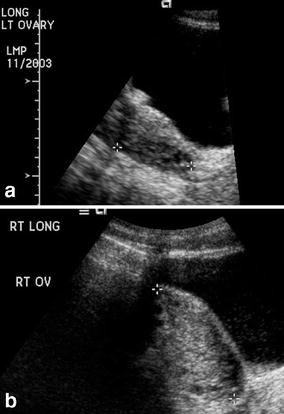

Adnexal torsion, including torsion of a normal or pathologic ovary, torsion of the fallopian tube, paratubal figure 2. Ct features of adnexal torsion. Malignancy in 16% of postmenopausal women vs.